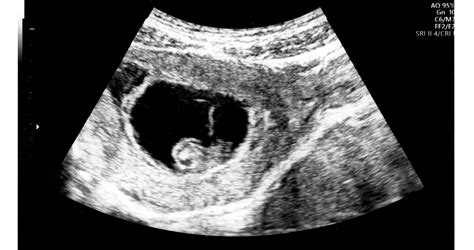

Az ultrahangos vizsgálatok fejlődésével egyre többet tudunk az ikerterhességekről. Azonban az esetek zömének csak egy gyermeke születik meg, a másik, fejletlenebb magzat a terhesség korai szakaszában elhal, és szinte nyomtalanul felszívódik a méhben. Ezt az "eltűnő iker" vagy "fantomiker" szindrómának nevezik.

Megsaccolni is nehéz, hány terhességet érinthet a fantomiker-jelenség. Kutatások szerint a várandósság 8. hetében a terhességek csaknem 5 százaléka ikerterhesség, viszont az egyik iker az esetek 21-30 százalékában eltűnik. Mesterséges megtermékenyítés esetén még gyakoribb a fantomiker-jelenség, az így született gyermekek akár 10-15 százalékának is lehetett a terhesség legkorábbi szakaszában egy "ikertestvére".